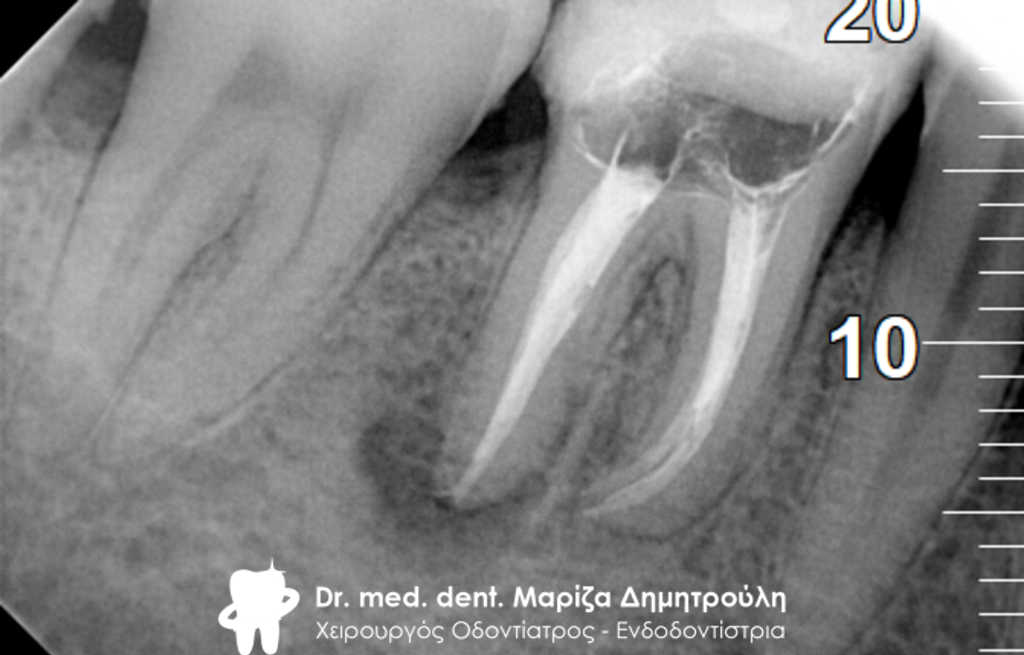

Ο ασθενής επιθυμούσε την προσθετική αποκατάσταση (με θήκη / στεφάνη δοντιού) του πρώτου γομφίου στην αριστερή πλευρά της κάτω γνάθου, καθώς το δόντι αυτό είχε ένα παλιό σφράγισμα το οποίο συνεχώς έσπαζε. Απαραίτητη προϋπόθεση για την έναρξη της διαδικασίας για τη στεφάνη δοντιού ήταν η κλινική και ακτινογραφική εξέταση του γομφίου. Μετά τη λήψη ακτινογραφίας αποκαλύφθηκε οτι το δόντι είχε μία παλιά απονεύρωση, η οποία ήταν ατελής εφόσον δεν εκτεινόταν σε όλο το μήκος των ριζικών σωλήνων του δοντιού ενώ φαινόταν ο τρίτος ριζικός σωλήνας στο δόντι να μην έχει εντοπιστεί. Μετά από συνεννόηση με τον ασθενή αποφασίστηκε η επανάληψη της απονεύρωσης του δοντιού, ώστε να εξασφαλιστεί ένα εγγυημένο προσθετικό αποτέλεσμα. Γενικότερα είναι επιθυμητό οι προσθετικές εργασίες να τοποθετούνται στα δόντια εφόσον έχουν γίνει όλες οι απαραίτητες εργασίες όπως απονεύρωση δοντιού, καθαρισμός των ούλων κ.α.

Μετά λοιπόν την αφαίρεση του παλιού σφραγίσματος εντοπίστηκε ο τρίτος ριζικός σωλήνας που δεν είχε βρεθεί στην παλιά πρώτη απονεύρωση, όπως δείχνει και η φωτογραφία της αρχικής κλινικής εικόνας. Στη συνέχεια καθαρίστηκαν και επεξεργάστηκαν όλοι οι ριζικοί σωλήνες (Για περισσότερες πληροφορίες Βλέπε Επανάληψη απονεύρωσης). Η διαδικασία ολοκληρώθηκε με την έμφραξη των ριζικών σωλήνων του δοντιού και την ανασύσταση της εκτεταμένης κοιλότητας με ειδικό άξονα υαλονημάτων και ρητίνη. Ακολούθως το δόντι τροχίστηκε, λήφθηκαν αποτυπώματα και όταν ο οδοντοτεχνίτης είχε έτοιμη τη θήκη του δοντιού αυτή κολλήθηκε στο δόντι.

ΠΡΙΝ